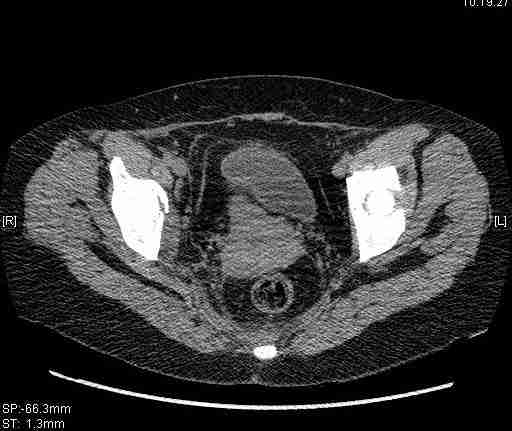

[Ortho] [1/2] Re: Т-образный перелом вертлужной впадины

Удалось сегодня вывести пациентку в соседнюю больницу, где есть кт.

Срезы сделаны  только горизонтальные.